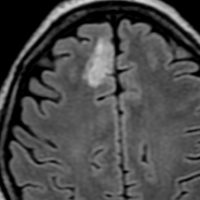

グレード2のオリゴ 乏突起膠腫

平均的な増大速度を示した乏突起膠腫グレード2です。左が無症状で発見された時,右が3年後で,ごくわずかに増大しています。開頭手術で摘出しました。